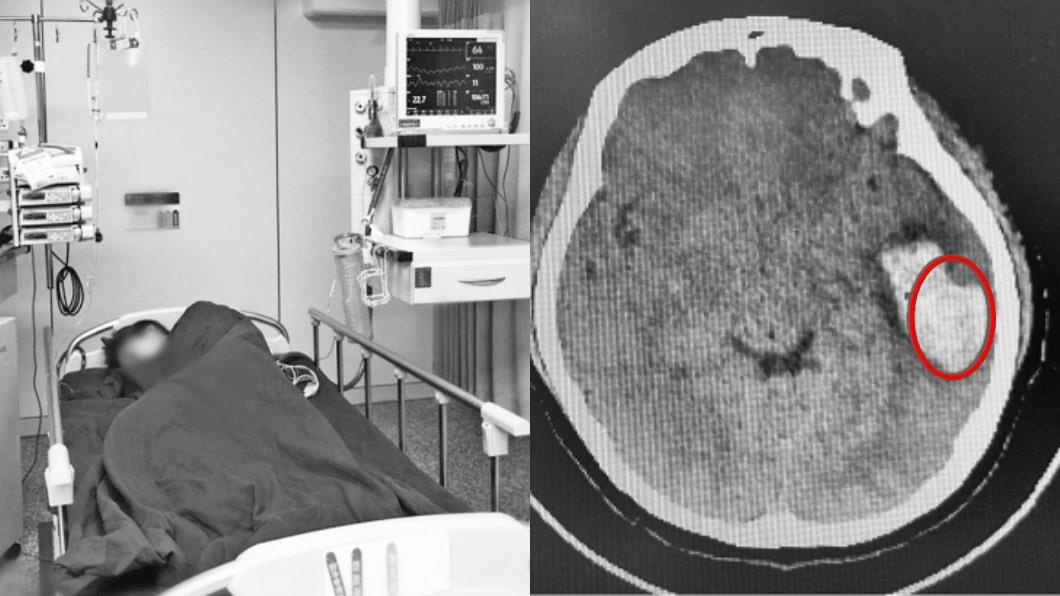

Cô được bạn bè đưa ngay đến Bệnh viện Đại học Trịnh Châu (Hà Nam, Trung Quốc) để cấp cứu. Kết quả chụp CT cho thấy mạch máu não của Hoan Hoan bị vỡ. Các bác sĩ còn phát hiện lượng lớn máu chảy ra, chèn ép vào các tổ chức não bộ, dây thần kinh. Đây là nguyên nhân trực tiếp dẫn đến việc cô cảm thấy buồn nôn và chóng mặt.

| Nữ sinh Hoan Hoan vỡ mạch máu khi hát karaoke, phải điều trị tại bệnh viện. Ảnh: hk01. |

Hoan Hoan được mổ cấp cứu để lấy khối máu tụ trong não, đề phòng biến chứng. Cô được theo dõi liên tục trong 72 giờ sau mổ cho đến khi đảm bảo không còn nguy cơ xảy ra biến chứng về não.